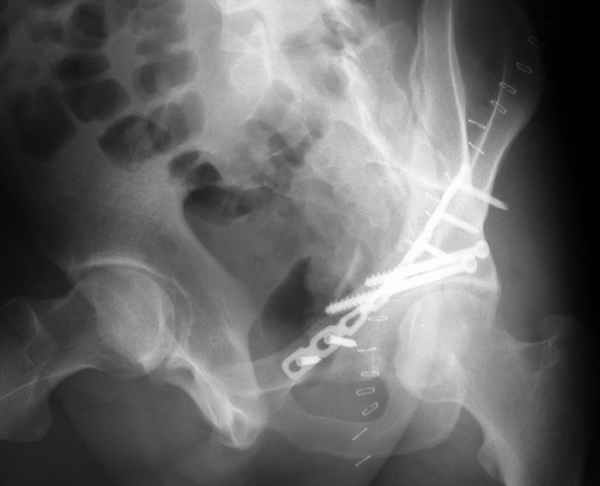

Конечно изнутри таза массивная гиперпластическая мозоль - пришлось немного попотеть и интерпозиция по плоскости перелома. Хорошо был виден ствол нерва с внутренней стороны вырезки - сделали блокаду, как положено. После операции движения стопы в полном объеме чувствительных расстройств нет. Репозиция удалась - мы были в легкой эйфории - внесуставной доступ и т.д. Через сутки стопа повисла - грубых выпадений на ЭНМГ нет, но тем не менее ишемический неврит малоберцовой порции седалищного нерва - бич застарелых повреждений.

Ах если бы Русские люди не обманывали себя и больных, а направляли бы срочно в специализированные отделения, то можно было бы получить хороший результат куда меньшей кровью пациентов и сердечных ран хирургов. Посылаю еще два снимка. Привет ЛАФ.